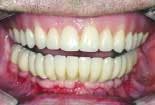

When the final restorations are received from the lab, they are inspected on the mounted models (figures 26 and 27). The final restoration is placed in the mouth and screwed in place. The access holes are filled with Clip, pink opaque composite and tooth-colored composite (figures 28 and 29). Final occlusal adjustments are made and esthetics confirmed (figure 30).

Utilization of the lower denture as a fixed provisional allowed for immediate loading of the dental implants. As well as allowing the patient to forgo the need to wear a lower denture, it also helps the restoring dentist in production of the final prosthesis. A fixed provisional lets us confirm the vertical dimension, occlusal scheme, and phonetics. The transition from the fixed provisional to the final restoration is then simple, requiring only a couple of appointments.